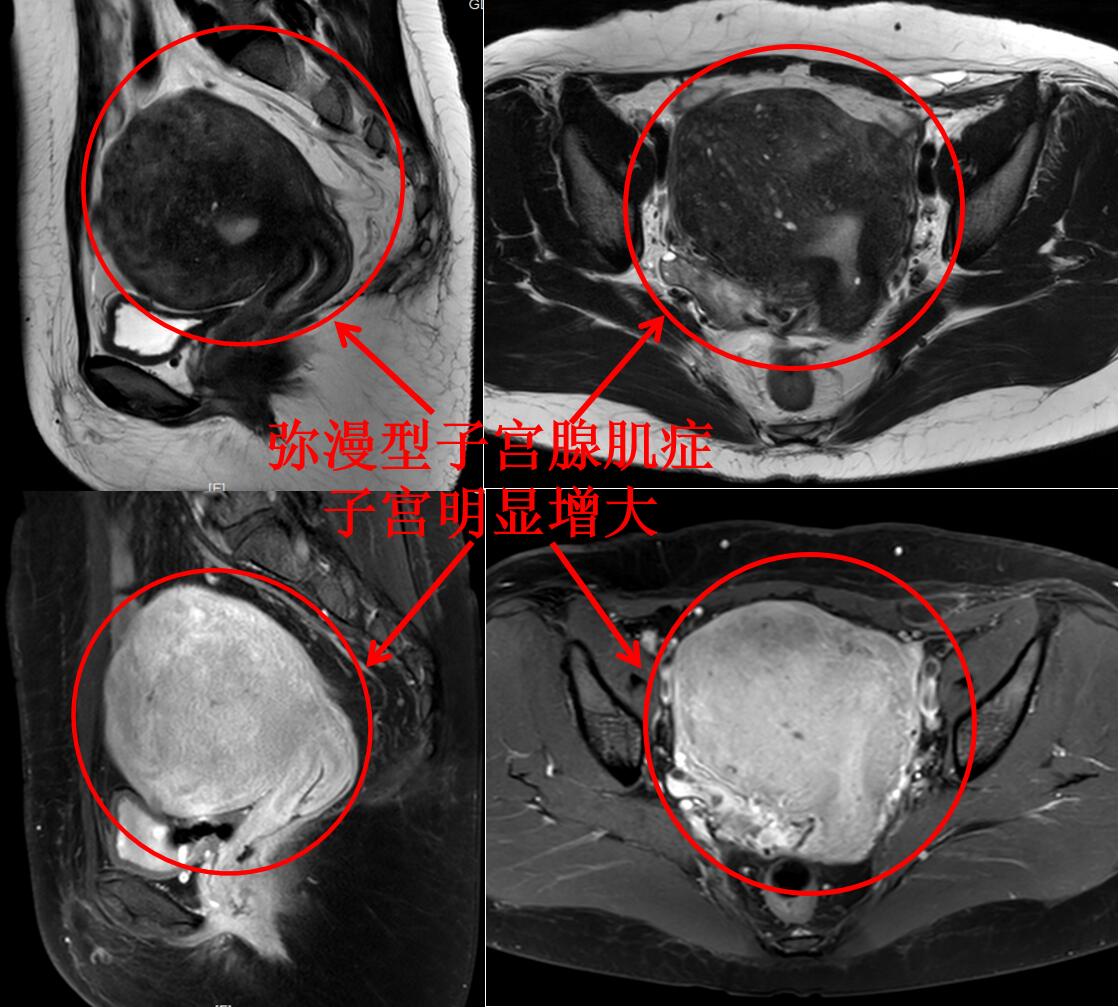

我们医院的蓝护士,8年前逐渐出现痛经,痛经在可以忍受的范围,不用服用止痛药,定期复查超声显示子宫逐渐增大。二胎后痛经逐渐加重,服用孕激素治疗,疼痛部分缓解,但月经老是拖尾,身体也逐渐发胖。近1年痛经再次加重,月经量增多而且经期延长十几天,月经还没干净几天,下一周期月经又来了,体重也严重超标。蓝护士就诊后考虑选择我院介入科的介入微创治疗,门诊磁共振检查显示:子宫明显增大(13.1*11.2*9.7cm3),腺肌症弥漫整个子宫,腺肌症病灶血供丰富。